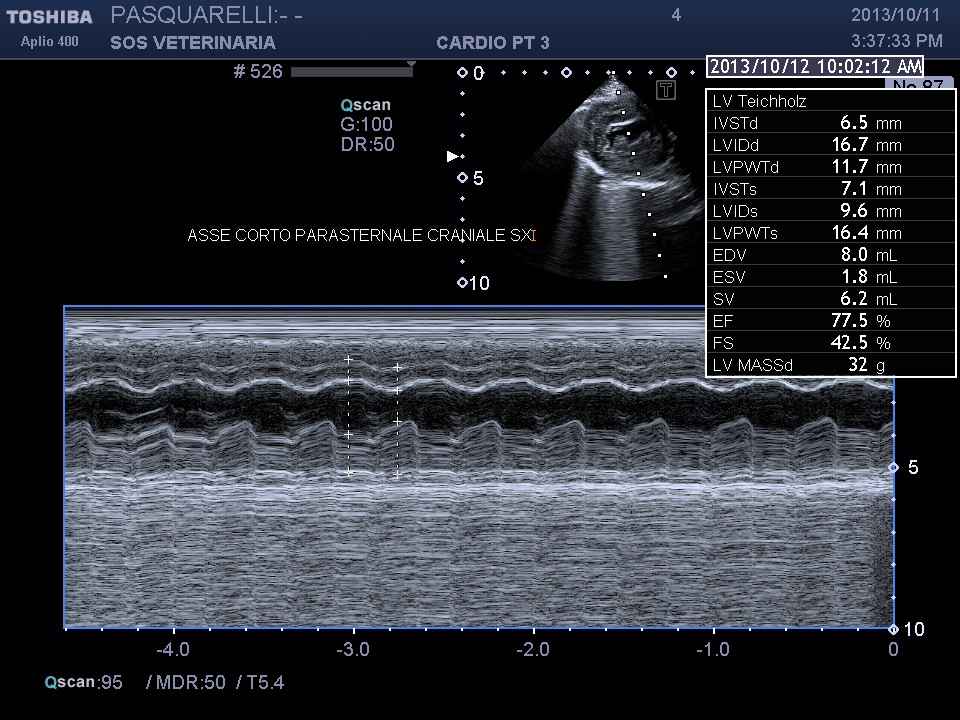

caso di cardiomiopatia ipertrofica del Maine Coone ,presentazione al pronto soccorso tipica con edema polmonare e tromboembolismo aortico completo bilaterale ,per la mia esperienza,nessun trattamento risulta essere efficace per questi soggetti, il decesso avviene nel 90%-95% dei casi e quelli che sopravvivono muoiono nelle settimane successive per le severe complicanze provocate dall’ipoperfusione ,i trattamenti trombolitici non risultano praticabili per diverse ragioni, non ultima quella economica, l’evento drammatico non e’ lo scompenso cardiaco diastolico (sul piano farmacologico gestibile) ma la trombosi aortica spesso anche polmonare .

Il soggetto aveva solo due anni di eta’ e aveva eseguito il test genico risultato negativo , da qui l’importanza, per una corretta analisi cardiologica ,dell’ecocardiogramma ,mai eseguito in questo caso .